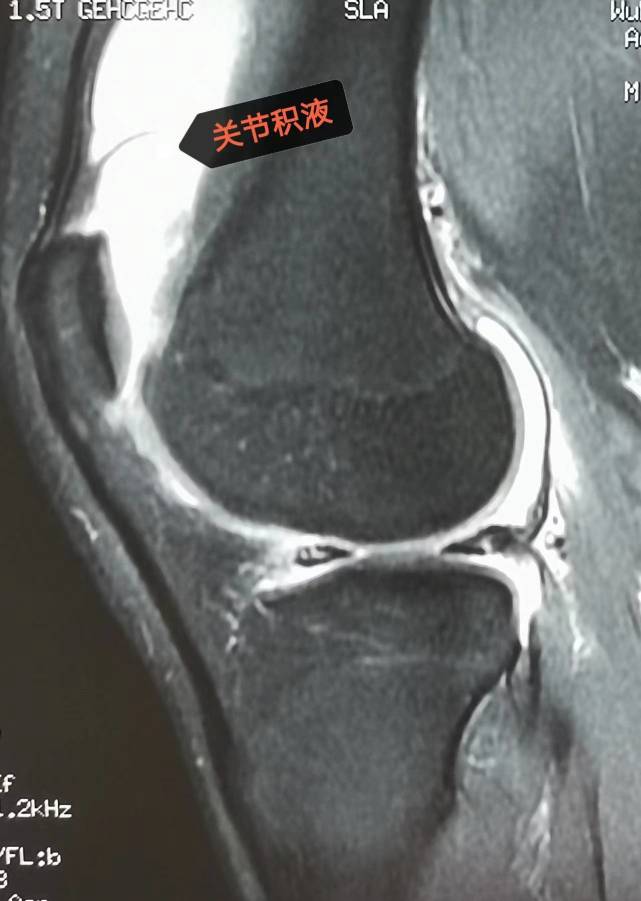

左膝关节mri